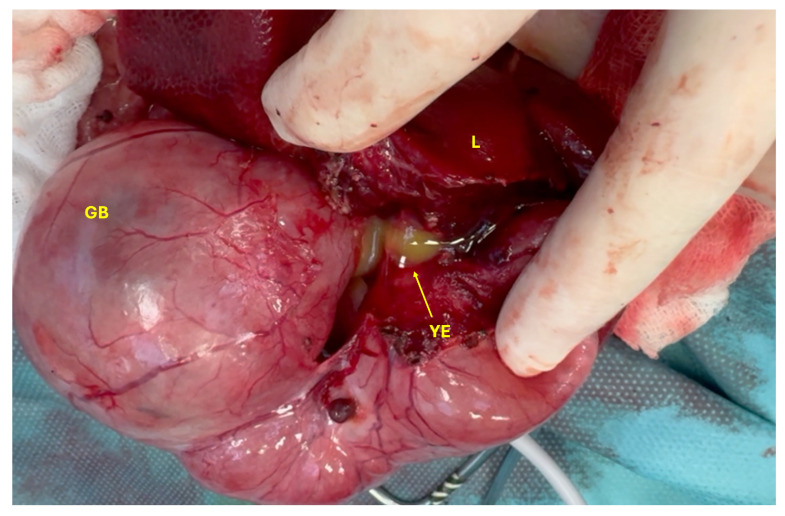

The cat was placed in dorsal recumbency, clipped, and aseptically prepared for surgery. Following clipping, the extent of the cranial abdominal enlargement was visible (Figure 3). Abdominal exploration revealed a markedly dilated gallbladder and CBD measuring approximately 10 × 7 cm, as well as hepatic ducts with an average diameter of 8 mm (Figure 4). The anatomical distinction between the gallbladder, cystic duct, and the CBD was no longer discernible. Additionally, the junction between the CBD and the duodenum at the level of the major duodenal papilla was severely dilated (Figure 5).

Both the gallbladder and CBD were filled with yellow exudate (a mixture of pus and bile), which began to leak from the liver upon initiation of dissection (Figure 6). Severe inflammation of the right arm of the pancreas was noted, along with dilation of the main pancreatic duct, which also contained yellow exudate. The stomach was empty and compressed, likely due to the mass effect exerted by the dilated gallbladder and CBD.